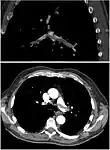

On CT scan, pulmonary emboli can be classified according to the level along the arterial tree.

Segmental and subsegmental pulmonary emboli on both sides

CT pulmonary angiography showing a "saddle embolus" at the bifurcation of the main pulmonary artery and thrombus burden in the lobar arteries on both sides.

Assessing the accuracy of CT pulmonary angiography is hindered by the rapid changes in the number of rows of detectors available in multidetector CT (MDCT) machines.[59] According to a cohort study, single-slice spiral CT may help diagnose detection among people with suspected pulmonary embolism.[60] In this study, the sensitivity was 69% and specificity was 84%. In this study which had a prevalence of detection was 32%, the positive predictive value of 67.0% and negative predictive value of 85.2%. However, this study's results may be biased due to possible incorporation bias, since the CT scan was the final diagnostic tool in people with pulmonary embolism. The authors noted that a negative single slice CT scan is insufficient to rule out pulmonary embolism on its own. A separate study with a mixture of 4 slice and 16 slice scanners reported a sensitivity of 83% and a specificity of 96%, which means that it is a good test for ruling out a pulmonary embolism if it is not seen on imaging and that it is very good at confirming a pulmonary embolism is present if it is seen. This study noted that additional testing is necessary when the clinical probability is inconsistent with the imaging results.[61] CTPA is non-inferior to VQ scanning, and identifies more emboli (without necessarily improving the outcome) compared to VQ scanning.[62]